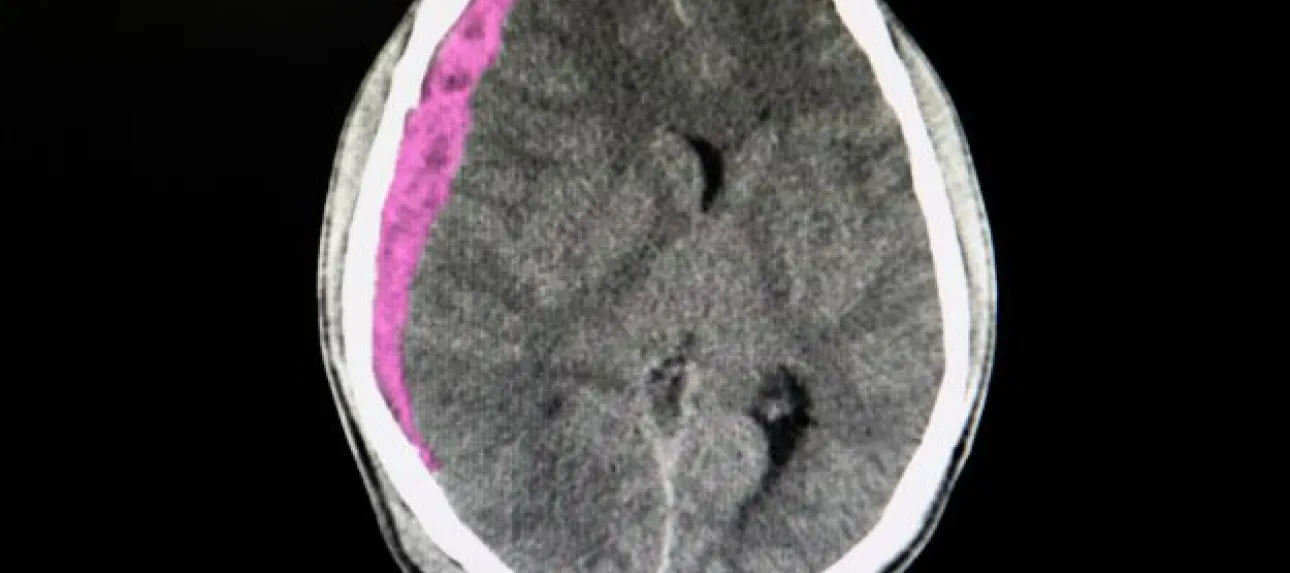

hematome sous dural

L'hématome sous-dural représente la complication la plus fréquente et la plus redoutable chez les seniors. Cette accumulation de sang entre le cerveau et la dure-mère peut se développer lentement, sur plusieurs jours ou semaines. Chez les personnes âgées, même un choc mineur peut provoquer cette lésion en raison de la fragilité accrue des vaisseaux sanguins et de l'atrophie cérébrale naturelle qui crée un espace plus important dans la boîte crânienne. Les symptômes peuvent inclure des maux de tête persistants, une somnolence progressive, des troubles de la mémoire ou des changements de comportement.